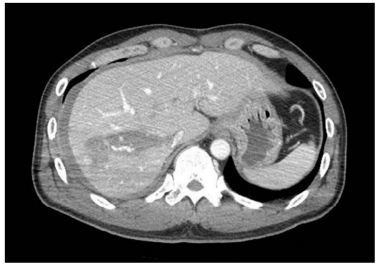

53세 남자가 1시간 전에 운전 중 트럭과 정면 충돌하여 응급실로 왔다. 혈압 100/60 mmHg, 맥박 110회/분, 호흡 22회/분, 체온 37.0ºC이다. 의식은 명료하다. 배 전체에 압통이 있으나 반동압통은 없다. 혈액검사 결과는 다음과 같다. 복부 컴퓨터 단층촬영 사진이다. 복강 내에 다른 장기는 손상되지 않았다. 조치는?

CT: Liver laceration with intraparenchymal hematoma (AAST grade II)

• 복부 CT에서 간의 laceration과 함께 intraparenchymal hematoma가 확인되며 AAST scale grade II 정도로 판단된다.

• 간 외상의 경우 혈역학적 불안정성에 따라 치료 접근 방법이 달라진다. V/S이 불안정하고 FAST상 free fluid가 보이는 경우 즉시 손상통제수술로 응급개복술을 시행해야 하나, 해당 증례는 V/S이 안정적이고 환자의 의식도 명료하므로 간동맥색전술을 시행하여야 한다.